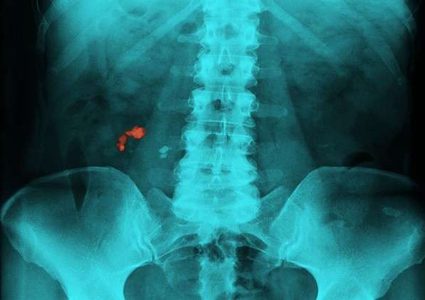

وضعت مجموعة من الأطباء، لائحة بالمنتجات الغذائية التي يجب الابتعاد عنها لأنها تسبب بتشكل الحصى في الكلى وتعطل عملها ونصح الباحثون بتجنب شرب القهوة (الشراب …